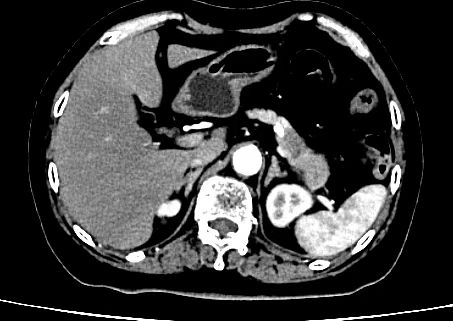

▲患者术前检查影像

“疼”,这是王女士给接诊医生张荷月留下的最深刻的印象。由于持续的腹部胀痛,加上当地医院给出的胰腺病变的怀疑,王女士和家人慕名来到了作为沈阳市胰腺疾病诊治中心的市六院寻求彻底治疗。经过详细检查,位于胰尾部直径约4.7厘米的肿物和显著升高的肿瘤标志物指标,让经验丰富的治疗团队作出了胰腺恶性肿瘤的判断,疾病随时可能威胁患者的生命。